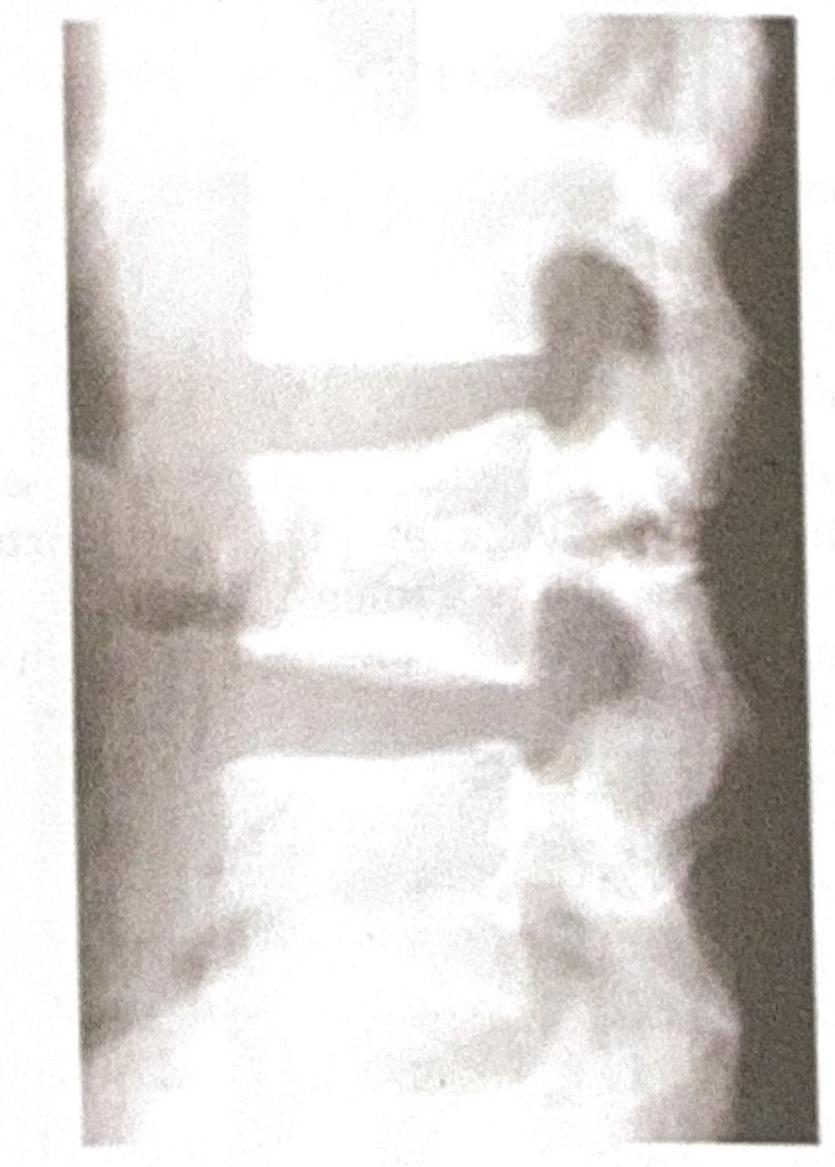

A 35-year-old male presents to the emergency department following a high-speed motor vehicle accident. He complains of severe lower back pain but denies any loss of consciousness or abdominal pain. A lateral X-ray of the lumbar spine is obtained, as shown in the image. The image reveals a horizontal fracture through the vertebral body, extending through the posterior elements. Based on the clinical presentation and imaging findings, what is the most likely diagnosis?

Explanation: ***Chance fracture*** - A **chance fracture** is characterized by a **horizontal fracture** through the entire vertebral body and posterior elements, including the neural arch, typically caused by a **flexion-distraction mechanism** in accidents like those involving seatbelts (lap belt only), consistent with the high-speed motor vehicle accident scenario. - The image distinctly shows a fracture line traversing the vertebral body and extending into the posterior elements, which is the hallmark of this type of injury. *Burst fracture* - A **burst fracture** involves a comminuted fracture of the vertebral body with **retropulsion of bone fragments** into the spinal canal due to axial loading, which is not clearly depicted here. - While it can result from high-impact trauma, the characteristic horizontal disruption of both anterior and posterior segments points away from a solely compressive mechanism. *Compression fracture* - A **compression fracture** primarily involves the **anterior wedging** or collapse of the vertebral body, resulting from only axial compression forces without significant involvement of the posterior elements. - The presented image shows a fracture extending through the posterior elements, which is not typical for a simple compression fracture. *Spondylolisthesis* - **Spondylolisthesis** is the **anterior slippage of one vertebral body over another**, often due to pars interarticularis defects (spondylolysis) or degenerative changes. - This condition involves vertebral displacement, not a fresh fracture line across the body and posterior elements as seen in the image.